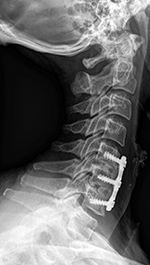

| An anterior cervical fixation plate and screws has been placed with PEEK disk cages at C5-6 and C6-7. |

The radiograph on the left was obtained on February 11, 2013. That on the right was obtained on July 22, 2015. It shows degenerative changes developing at the C4-5 disk space above the anterior fusion going from C5-7. |